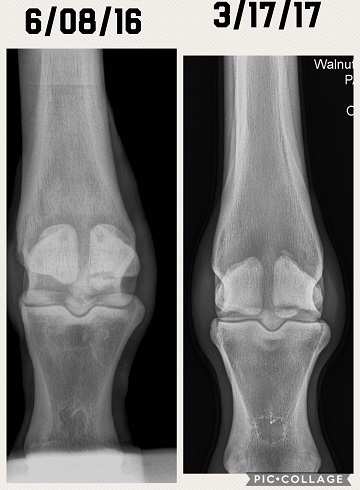

Just wanting to see if anyone had any opinions on these X-rays. Diagnosis was a fractured sesamoid bone. Before and after X-rays in the pics. Do they look any better? Does he have any hope for a barrel future? Anyone experienced this before? Completely sound in the pasture at this time. Has not been put back to work yet. Thanks man advance.

(xray 1.JPG)

(xray 2.JPG)

(xray3.JPG)

(6-1-16 side2.jpg)

Still looks like a chip is floating around in there.

How old is this horse? I do see what looks like a bone chip floating around

The vet has said it has calcified some. He hasn't said anything about a chip in there. I don't know if it is something that will break off or just calcify and heal up in the next few years.